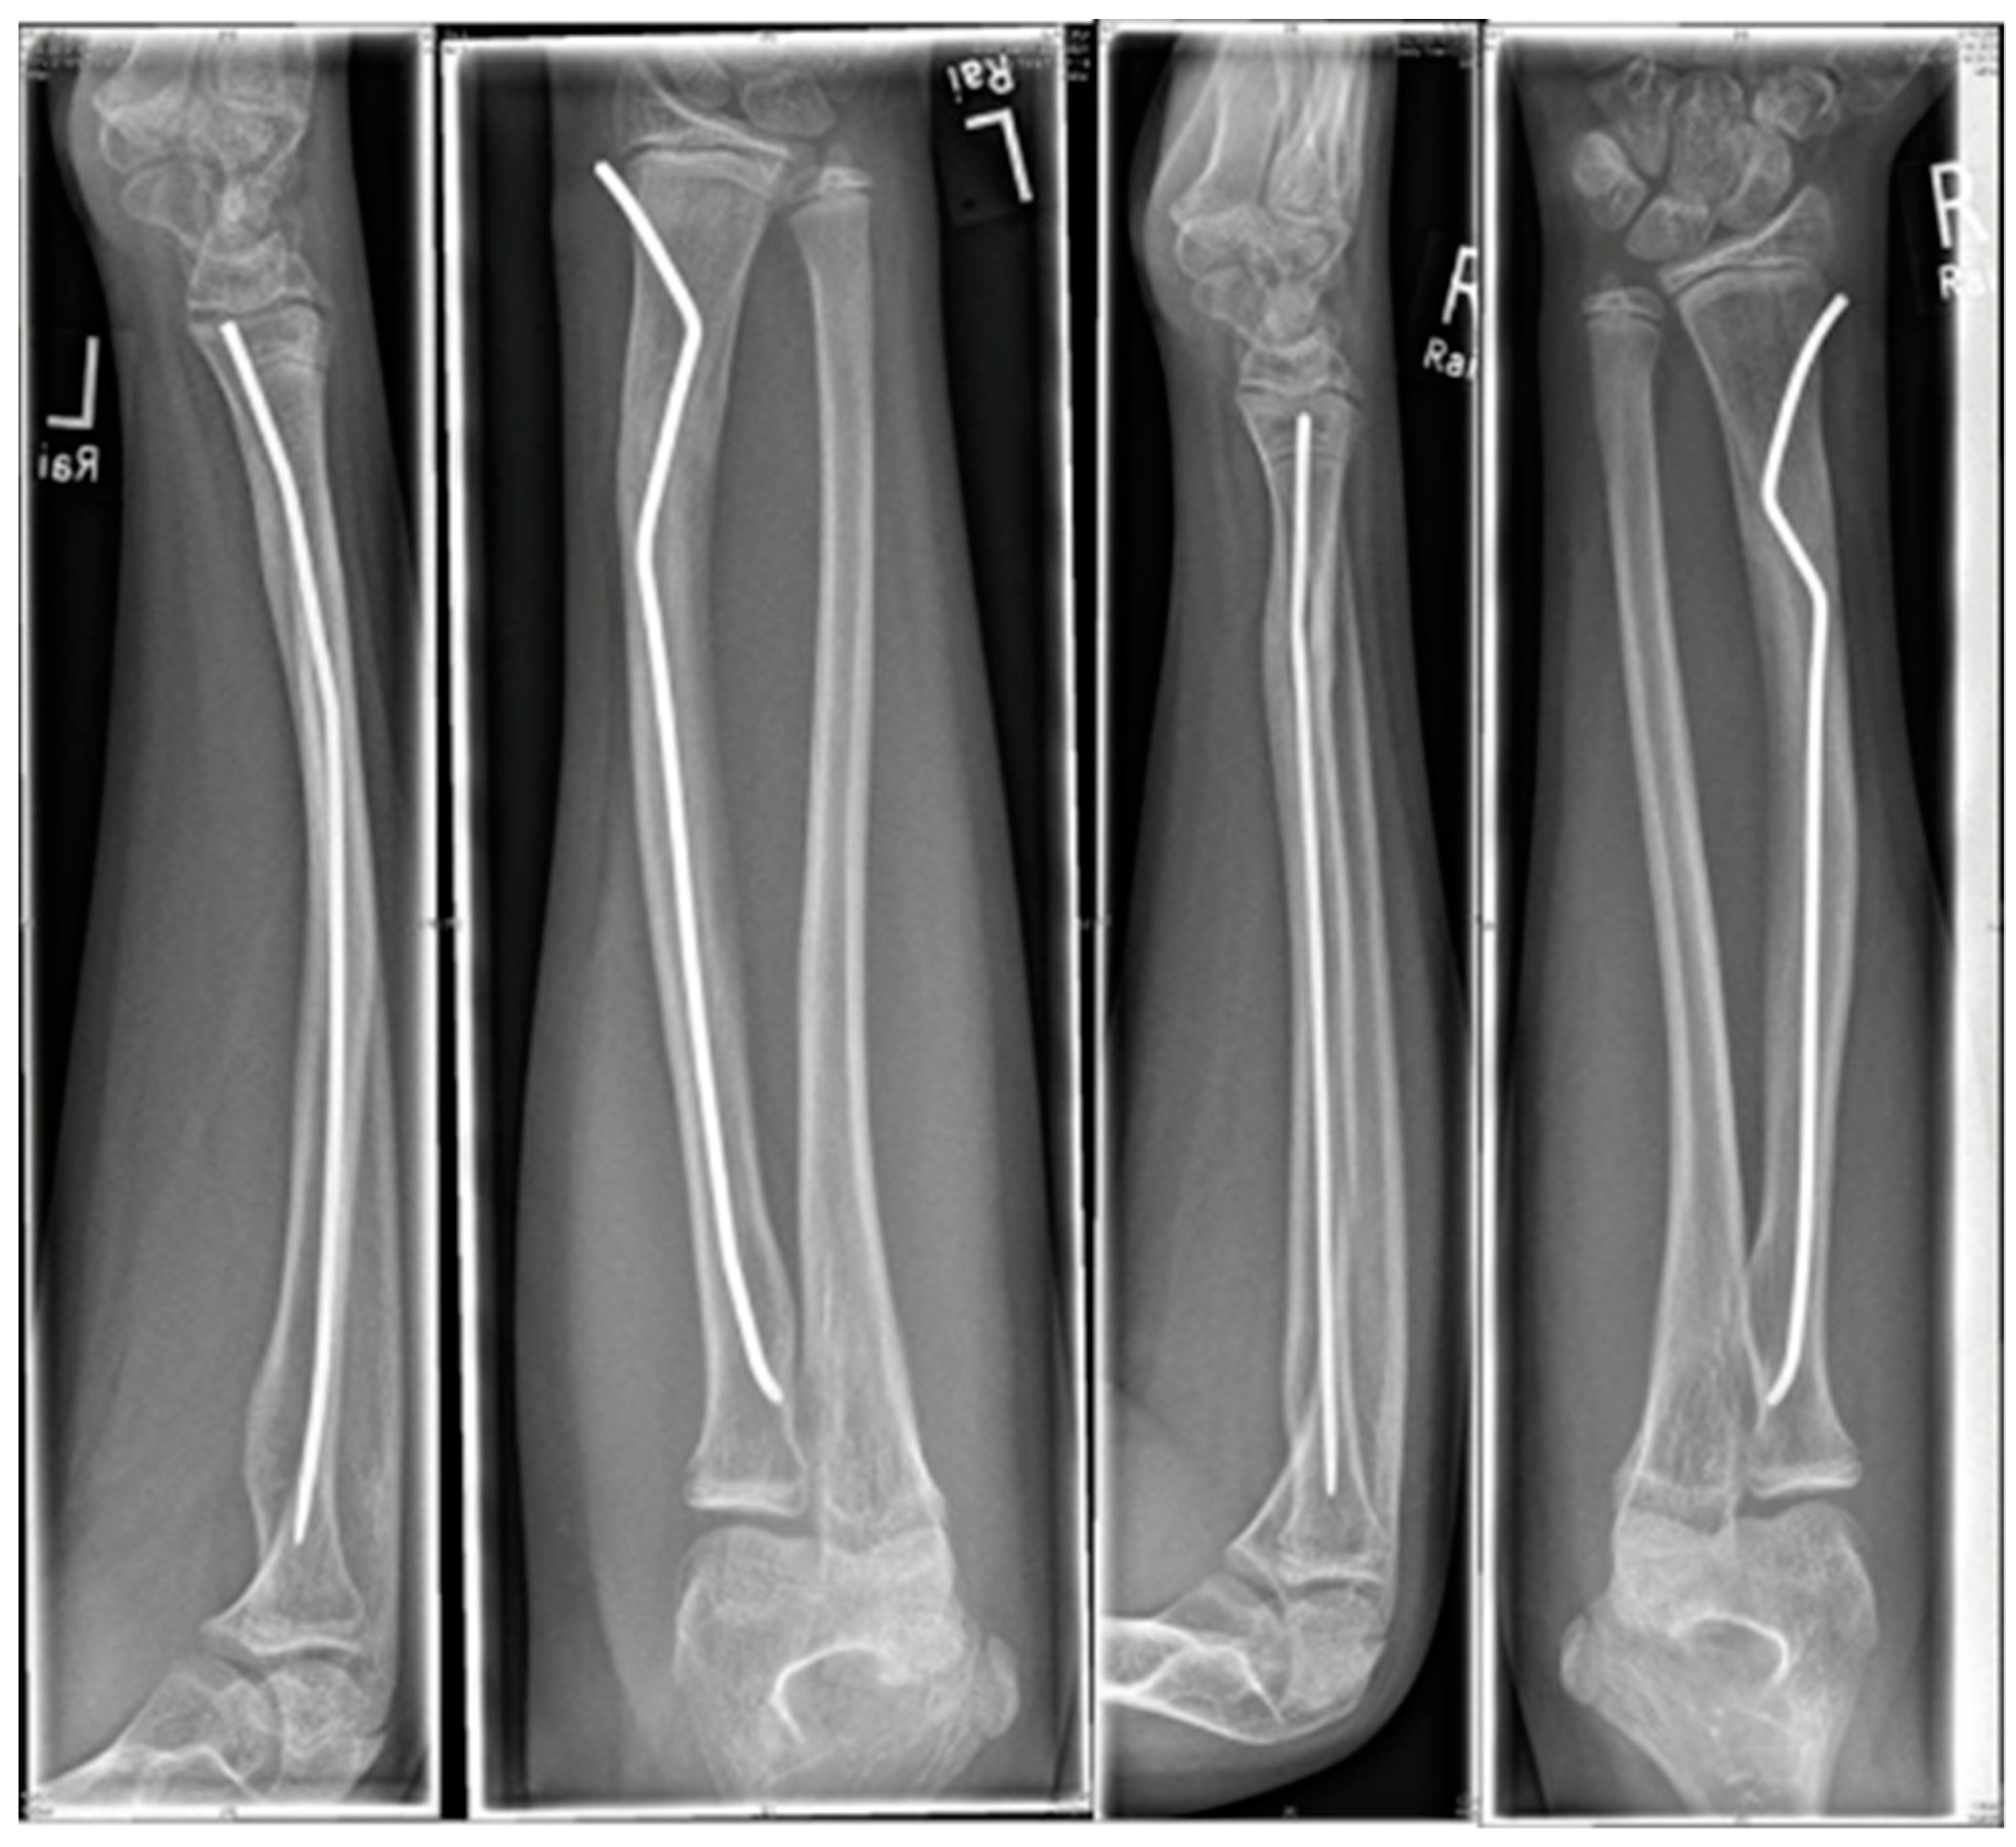

Scheme 5. Patient with identical fractures in both arms.

The youngest patient was a two-year old boy, who presented with an unacceptable secondary displacement two weeks after trauma and, thus, this fracture became a rare indication for osteosynthesis in this age group (Scheme 2). The eldest was 17 years of age and did not show epiphyseal plates anymore (Scheme 3). This patient, however, suffered a new trauma 3 weeks later and underwent a redo-procedure in another hospital and, thus, was lost to follow-up. We even treated an open forearm fracture (on the ulnar side) with this technique (Scheme 4), leaving the fracture of the ulna to spontaneous healing and correction. This was because the risk of osteomyelitis due to intramedullary nailing of the open ulnar fracture to achieve a “nice X-ray” was estimated to be much higher than the risk of a remaining misalignment. Even a redo-procedure of a fracture that we had seen for the first time 4 weeks after an unacceptable K-wire osteosynthesis was successful, this time using a modification of the technique with a bend, rather than a kink distal to the fracture. Please note that the pre-bent nail pushed the 4-week-old fracture into a correct position without open reduction (Scheme 4). Last but not least, curiously, we saw one patient who suffered identical fractures in both arms, so we could perform the procedure twice in one operation (Scheme 5).